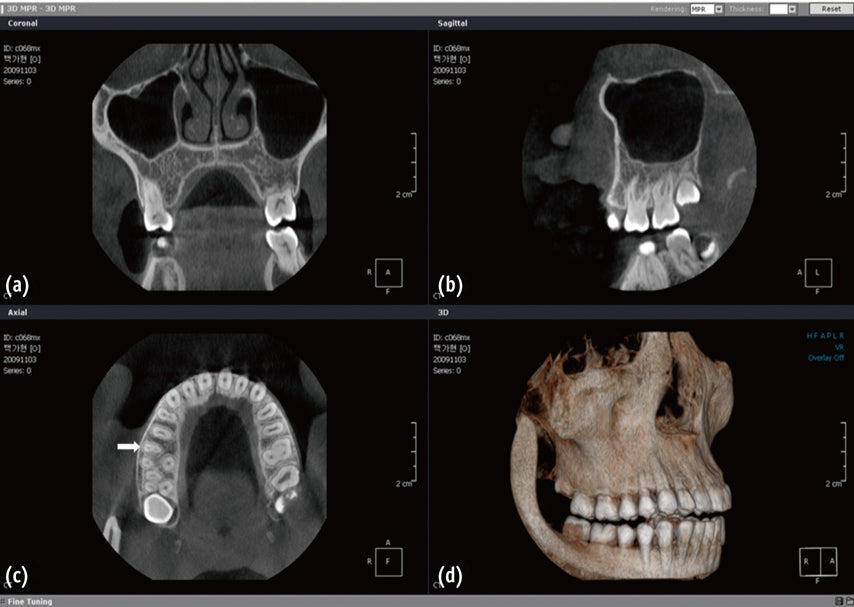

Rising Demand in Dentistry: Mexico’s Cone-Beam Computed Tomography (CBCT) market is significantly driven by the increasing demand for dental imaging solutions. CBCT is highly sought after for its ability to provide precise 3D imaging of dental structures, which is essential for dental implantology, orthodontics, and endodontics.

Expanding Dental Implant Market: The growing popularity of dental implants in Mexico is one of the key drivers of the CBCT market. The need for accurate pre-surgical assessment and precise implant placement is boosting the demand for CBCT, which provides detailed 3D images that enhance implant planning.

Increasing Prevalence of Dental Disorders: The rising prevalence of dental disorders in Mexico, such as periodontitis, tooth decay, and malocclusion, is fueling the demand for advanced diagnostic tools like CBCT. The technology allows for more accurate diagnosis and treatment planning, thereby improving patient care.

The Cone-Beam Computed Tomography (CBCT) Systems Market in Mexico is experiencing robust growth, primarily driven by its applications in dentistry, particularly dental implants and orthodontics. The adoption of advanced CBCT technologies offering improved imaging capabilities, lower radiation exposure, and integration with digital tools is enhancing the treatment planning process in both dental and medical practices. With government support, increasing awareness, and rising demand for accurate diagnostic solutions, CBCT systems are set to become an integral part of Mexico's healthcare landscape, especially in dental and maxillofacial treatments.